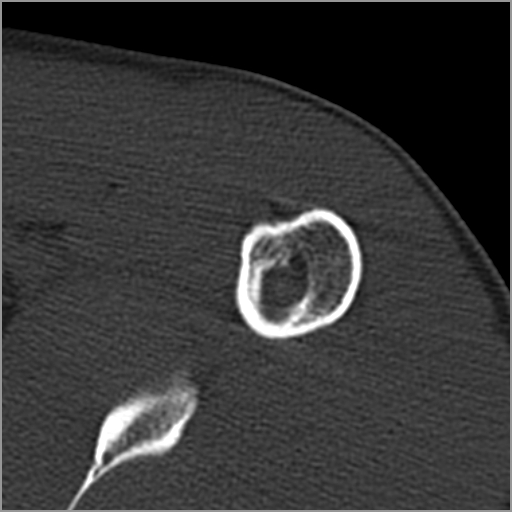

以下是引用zxd95在2008-7-19 18:45:00的发言:[br]囊性病灶边缘硬化、皮质变薄但连续——提示生长时间长、良性病变——考虑左肱骨头骨囊肿。[br]

以下是引用杀毒软件在2008-7-19 18:55:00的发言:[br]考虑:骨巨细胞瘤可能性大